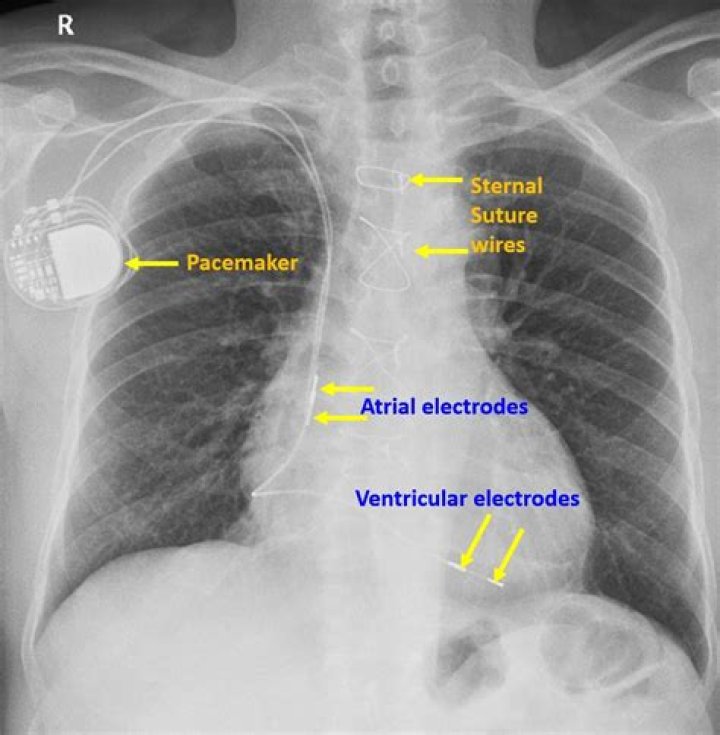

The pacemaker is a small metal case that contains electronic circuitry and a battery. The pacemaker continually monitors the heart and sends an electrical impulse to pace the heart when the heart’s own rhythm is interrupted, irregular, or too slow.

Can you have an xray with a pacemaker?

X-rays, such as those used in CT or CAT scans, don’t appear to interfere with pacemakers. Still, always alert the imaging technicians that you have a pacemaker implanted before undergoing a CT or CAT scan.